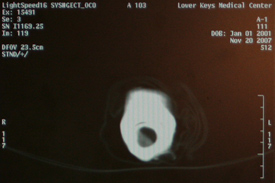

Our Senior Conservator, John, was on call for 3 days with Mechelle Buffington, a CAT Scan technician at the Lower Keys Medical Center. When she finally had a lull between patients John brought 13 artifacts including arquebus, sword handles and daggers to the medical center. The swords and arquebus CAT Scan images were captured separately and the daggers were scanned in a group. The whole process took 2 hours because after the scans were taken John, with Mechelle’s help, was able to study the images on the computer screen and decide how to adjust the resolution of the image to fit his purposes. After he was satisfied with the images on the computer screen they were printed out into film medium so he would be able to bring them back to the conservation lab with him. While he is working on each artifact the film will be backlit immediately in front of the artifact he is working on so he knows exactly which area of the artifact he is dealing with and can properly conserve the item.

From what John can tell so far the arquebuses looked great, the muzzle end may be a bit eroded. Early views of the films show that there are parts missing on the sword handles and the daggers are still being studied. The handles look to be in good condition but we are unable to draw any conclusions about the blades as of yet.